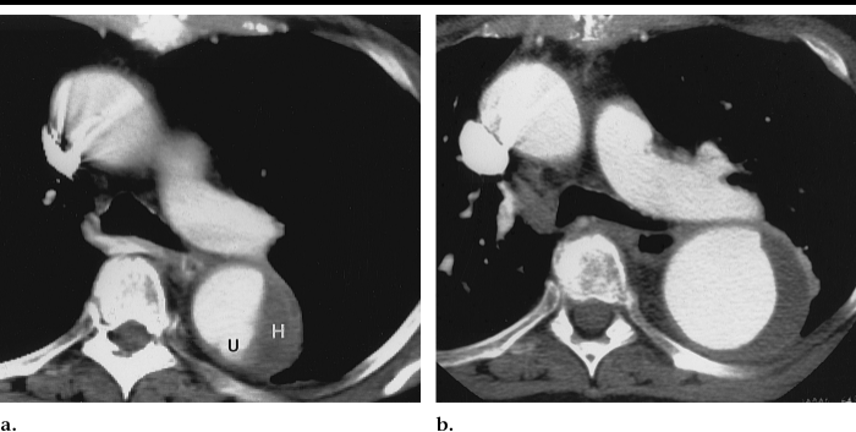

一线诊断手段:CT是PAU的一线诊断手段

腹主动脉PAU:伴血肿(假性动脉瘤)、栓塞症状、复发性疼痛为手术指征,非复杂型应考虑保守治疗。

包括腔内治疗、开放手术。文中列举了多个通过腔内治疗(如预开豁口、原位开窗、一体式分支支架等)和开放手术治疗PAU的病例。